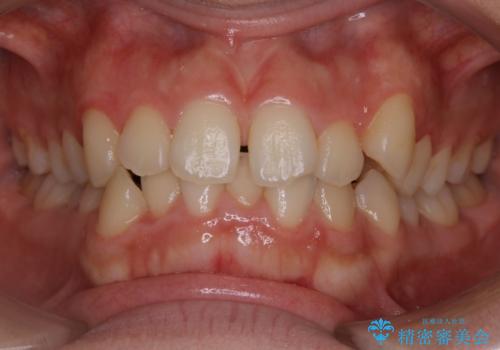

- 上の前歯のすきっ歯と下の前歯のガタつきを主訴にご来院されました。

噛み合わせの改善も同時に進めつつ、主訴の部分も効率的に治していくためマウスピース装置でゴムかけを行いながら治療を進めていきました。

正中離開(すきっ歯)

真ん中の歯が左右に開いてしまい隙間ができてしまう状態を「正中離開」といい、俗にすきっ歯と呼ばれています。

隙間を埋めていく方向に歯を移動させることで改善していくケースが多く、比較的治りやすい不正咬合のひとつとされています。

しかしながら、歯が捻じれていたり、噛み合う歯との位置関係によっては治療が難しくなる場合があります。